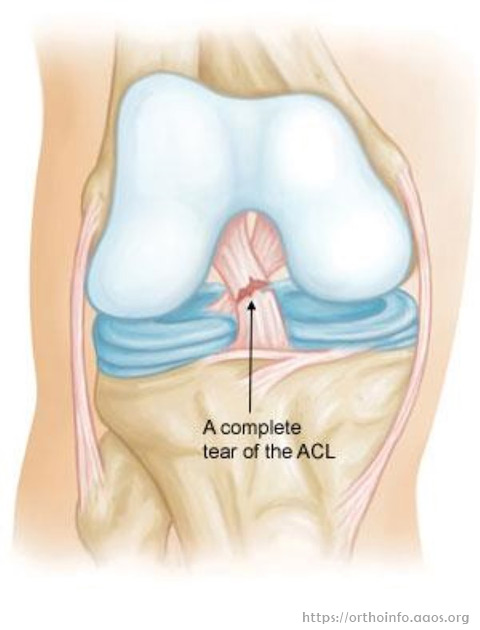

但由於前十字韌帶的特別生理構造,自我癒合能力很低。

保守治療等的成功率約有三成。

手術治療:

研究顯示膝關節如缺乏前十字韌帶,半月板及軟骨受傷機會將大大增加,繼而導致關節過早退化。因此如患者年輕及活躍於運動,醫生多會建議手術。但如前題所述,前十字韌帶的生理構造特別,直接修補如縫針失敗率非常高,因此一般需作重建。

前十字韌帶重建手術是十分普遍,技術也很成熟的手術。

單在美國每年便有超過十萬宗手術個案。

成功率可超過九成,即經過手術後病人均感到滿意及重回運動。